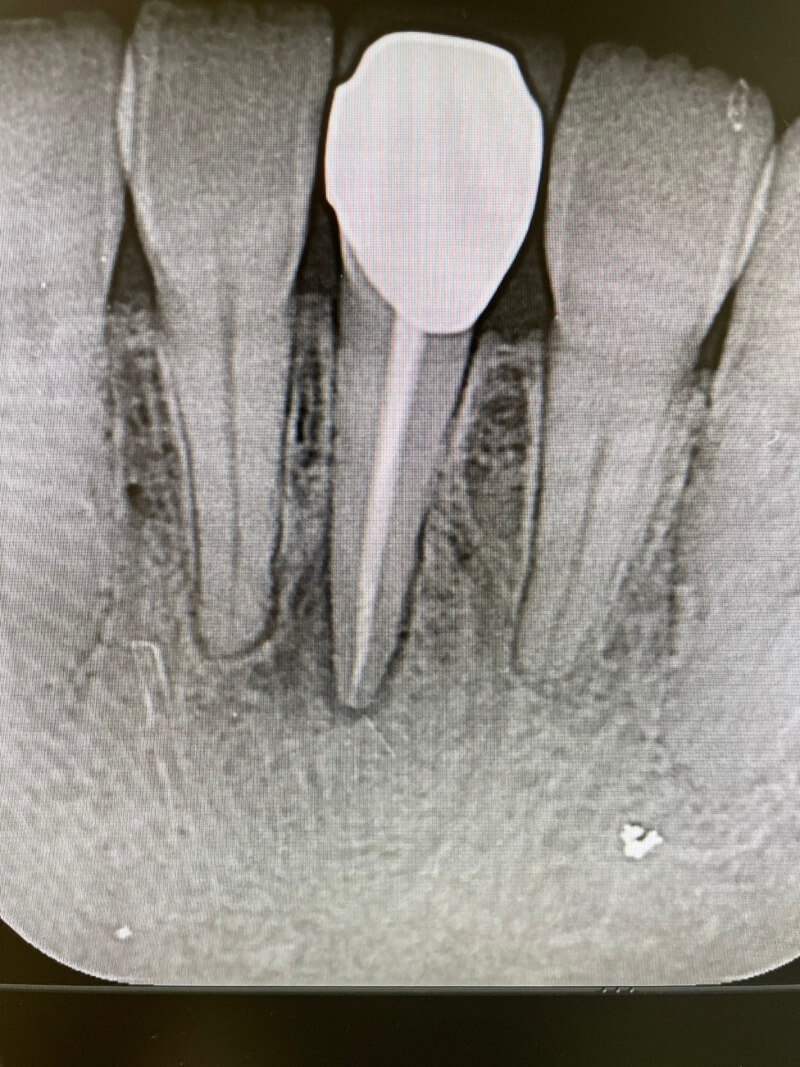

歯周嚢胞(ししゅうのうほう)は炎症性あるいは発育性の歯原性嚢胞の一つ。通常、萌出中の大臼歯の歯冠や歯根に関連して出現する。この嚢胞が萌出中の第三大臼歯の遠心(同部に発生する歯周嚢胞をHofrath嚢胞と呼ぶ。)や歯列の他の場所で成長すると、単に歯周嚢胞と呼ばれる。しかし、6歳から10歳の下顎第一大臼歯頬側根分岐部に発生した嚢胞はbuccal bifurcation cystと呼び、これは他の歯周嚢胞と比較して特徴的な臨床的特徴を持ち、管理における考慮が必要である。